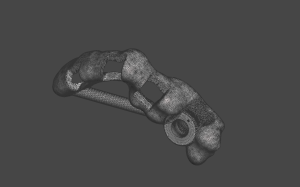

Curso Meshmixer

Herramientas básicas de manejo del software Preparación del modelo Librerías / Exodoncias virtuales Encerados Rodetes digitales Y más… Meshmixer